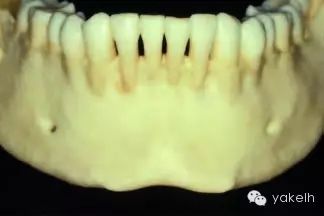

¤¤許多上頜竇以及Onlay植骨的移植物來自于下頜骨頦部。已有報道從下頜骨前牙區(qū)獲取塊狀骨以及顆粒狀骨的技術(shù)。頦部是口內(nèi)能提供最大骨量的區(qū)域(圖13.15)。兩頦孔間的平均距離為5cm,平均厚度為1cm。CT掃描以及全景片能夠評估該區(qū)的可供骨量。頭影測量片可測定下頜骨前牙區(qū)的前后徑。根尖片能更精確地測量牙根長度。

圖13.15 干燥的標(biāo)本提示,從下頜骨頦部可以獲取大量的骨質(zhì)。